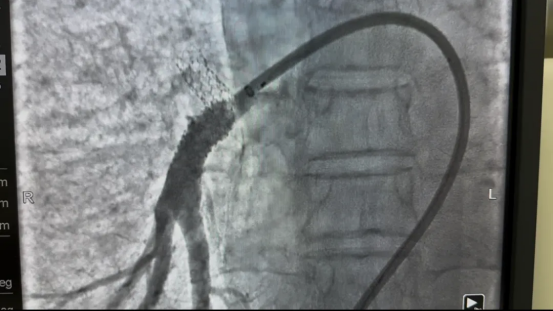

面对这一药物治疗效果有限、外科手术风险高的疾病,医疗团队制定了“微创、安全、有效” 的介入治疗方案。通过分次实施肺动脉成形术,逐步解除肺动脉狭窄,降低肺动脉压力。

疗效立竿见影。首次术后三天,张先生自觉气喘、胸闷明显缓解,阵发性干咳亦可耐受,肺动脉压降至66mmHg。完成三次手术后,他的肺动脉压已接近正常水平(40mmHg),日常活动完全不受限制,生活质量显著提升。